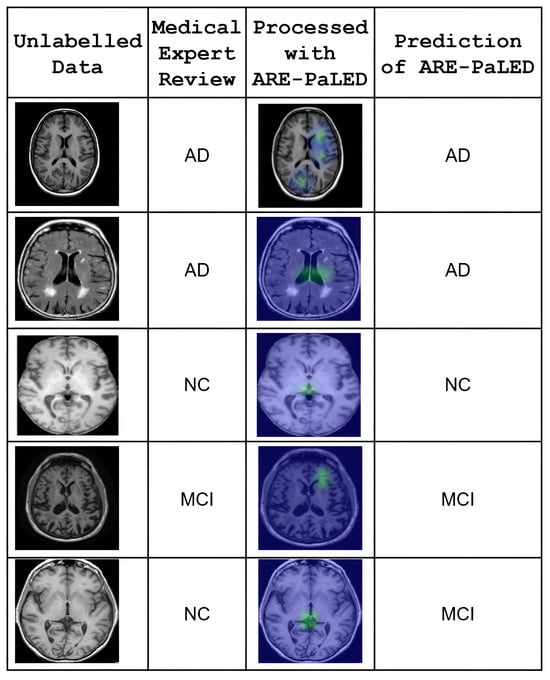

6.6. Empirical Support and Preliminary Validation

Preliminary empirical support for the practical applicability of our model is provided by an additional test that was conducted using a small set of previously unlabeled sMRI scans. These scans were retrospectively reviewed and labelled by qualified medical experts to establish reference diagnoses. The performance of ARE-PaLED was then evaluated on these expert-labelled cases using the same trained model without further fine-tuning. The model demonstrated consistent classification outcomes that aligned with expert labels in most cases, suggesting its generalisability to unseen data. Figure 8 demonstrates the empirical applicability and diagnostic consistency of the ARE-PaLED framework on previously unlabeled MRI data. The interpretability of the XAI outputs along with AR-based visualisations produced by ARE-PaLED was validated through expert review, with clinicians confirming their relevance and utility in supporting diagnostic decisions.